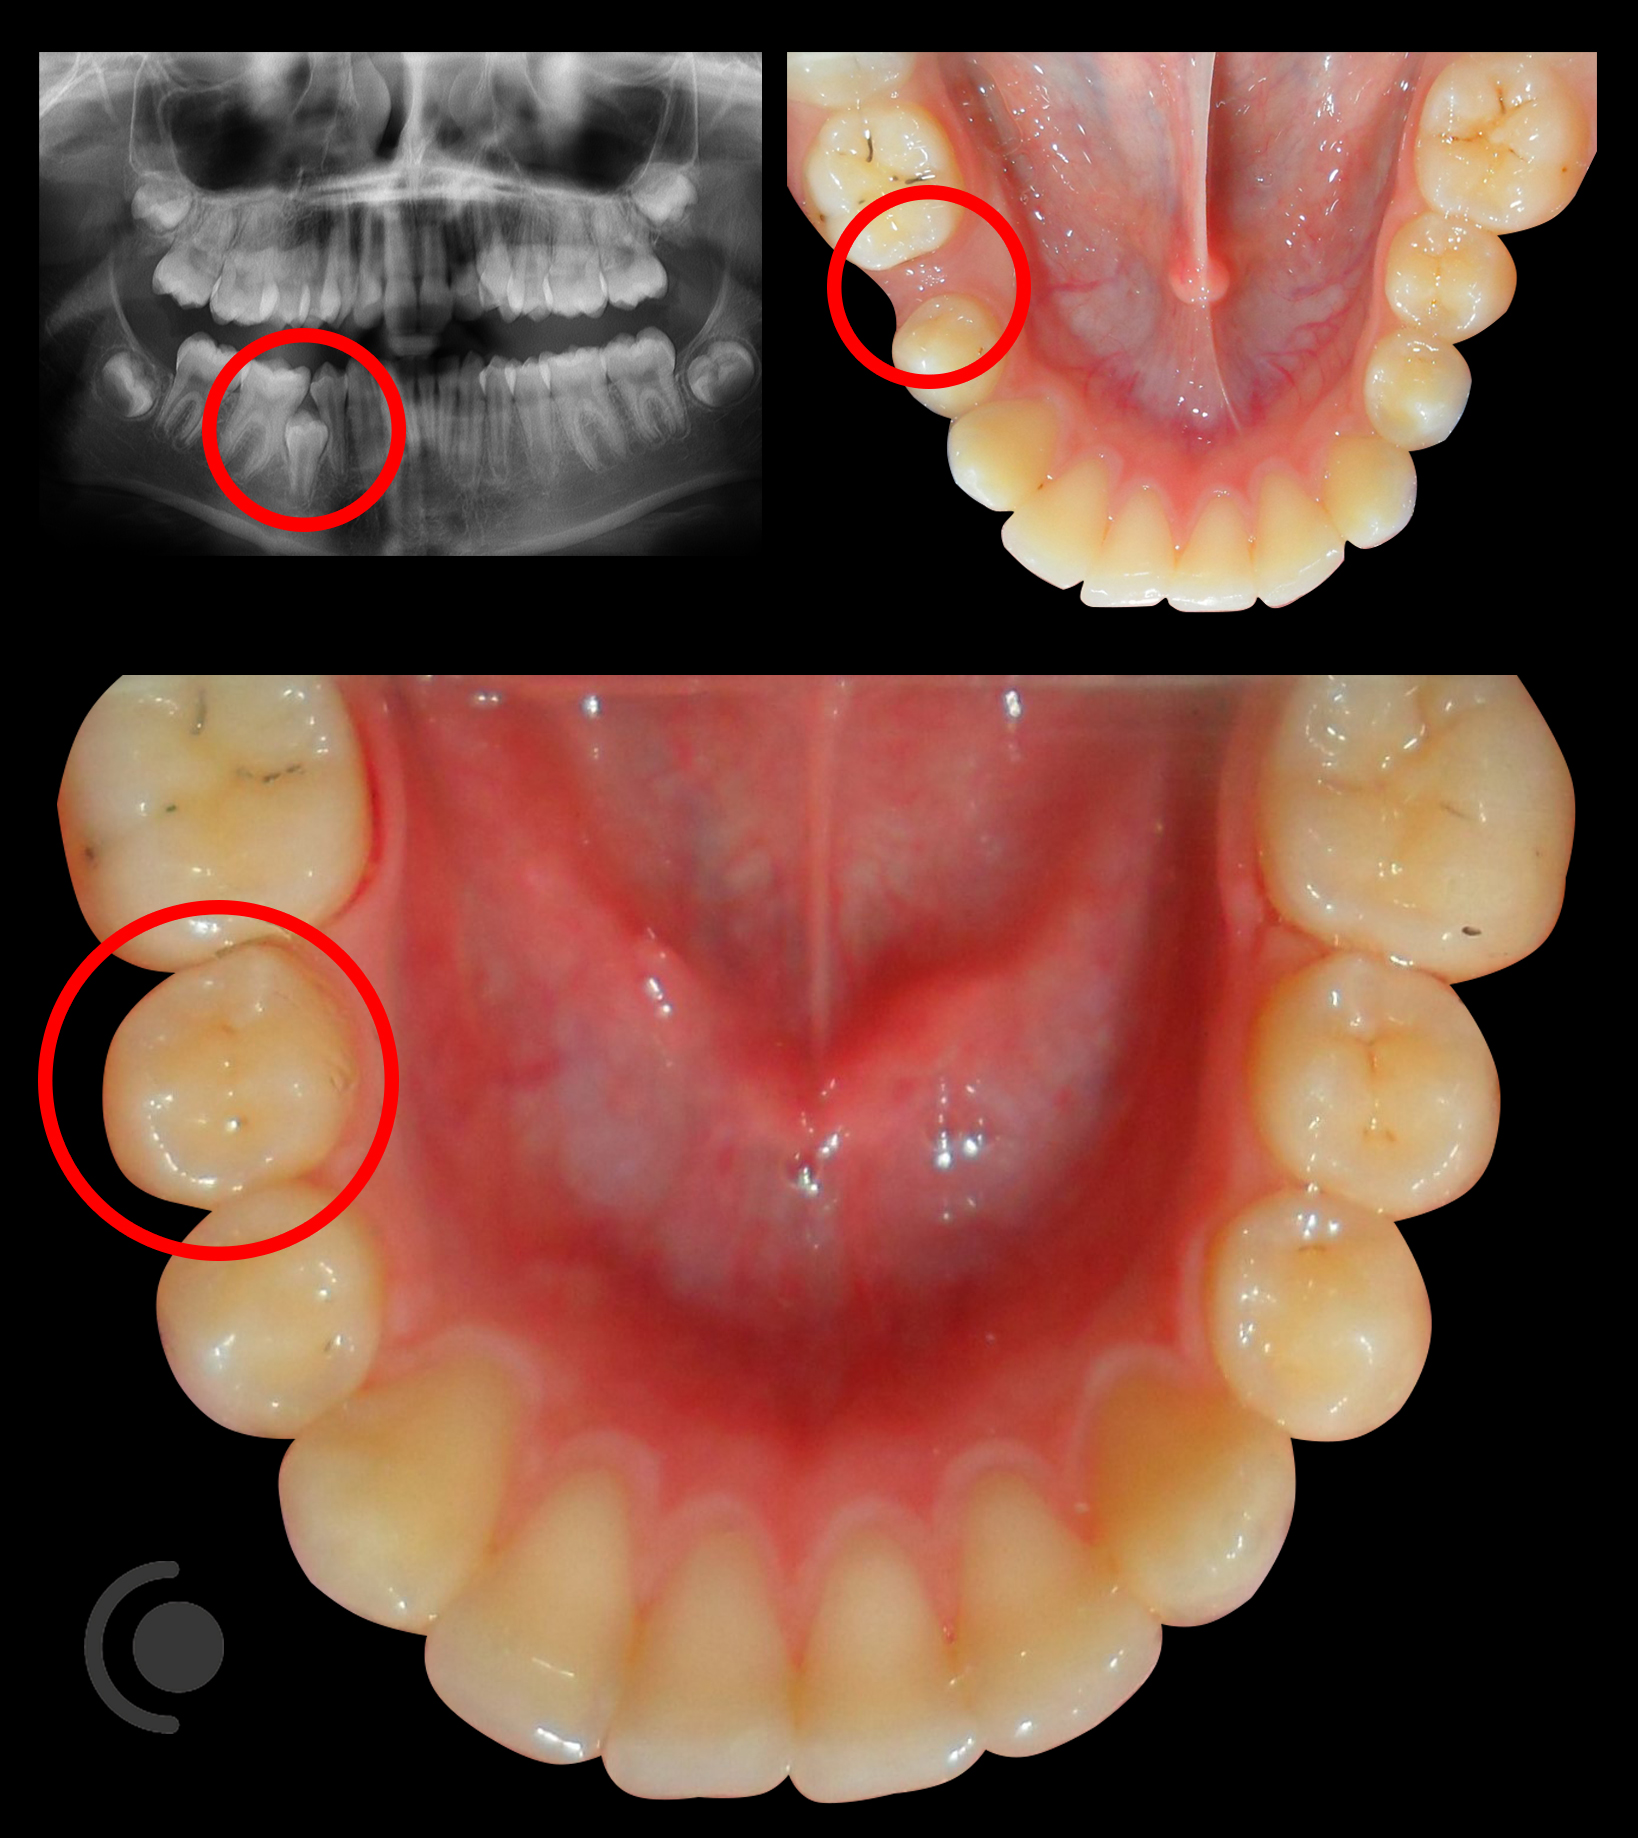

Ortodontsko izvlačenje neizniklih zubi. Ponekad zubi ne izniknu na svojem mjestu niti na bilo kojem mjestu unutar zubnog luka. Takvi zubi se zovu retinirani i